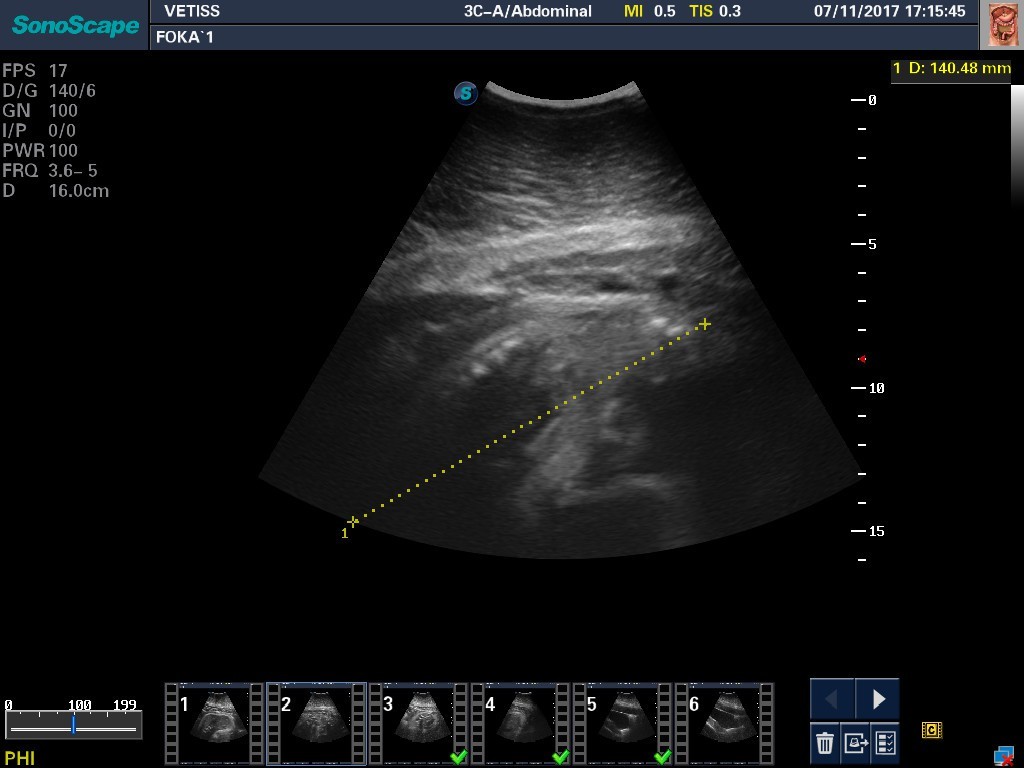

W helskim fokarium już niedługo na świat przyjdą dwa focze szczenięta. Poród planowany jest na przełomie lutego i marca. Gdy młode foki dorosną, dołączą do tych dziko żyjących w morzu. To efekt trwającego od lat 90. programu odtworzenia populacji fok w Bałtyku.

Ciąża u foki trwa 11,5 miesiąca, zawsze jest pojedyncza. Po przyjściu na świat młode są przysposabiane do życia w warunkach naturalnych i wypuszczane do morza.

Co roku samica wydaje szczenię. Na przełomie lutego i marca są porody. Zaraz po porodach jest okres godowy. Taka samica zwykle zachodzi w ciążę i równo po 11,5 miesiąca wydaje na świat kolejne szczenię – informuje Jerzy Marks, opiekun fok w helskim fokarium.

Szczenięta będą karmione przez około trzy tygodnie mlekiem z zawartością około 50 procent tłuszczu.

Na takiej pożywce, szczenię rośnie bardzo szybko. Potrafi przybierać około 2,5 kg dziennie. Jest pod bardzo dobrą i troskliwą opieką matki – dodaje Jerzy Marks.